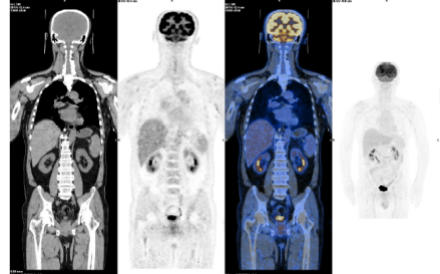

患者使用第3周期塞利尼索联合地西他滨和R-Gemoxd方案进行化疗后,行T细胞采集,拟进行CAR-T细胞治疗,随后再次使用1个疗程塞利尼索联合地西他滨和R-Gemoxd方案化疗,复查PET/CT显示:持续CR。回输CAR-T细胞后复查PET/CT显示:持续CR。

上图:CAR-T治疗前PET/CT显示:CR

下图:CAR-T回输后1月复查PET/CT显示:CR